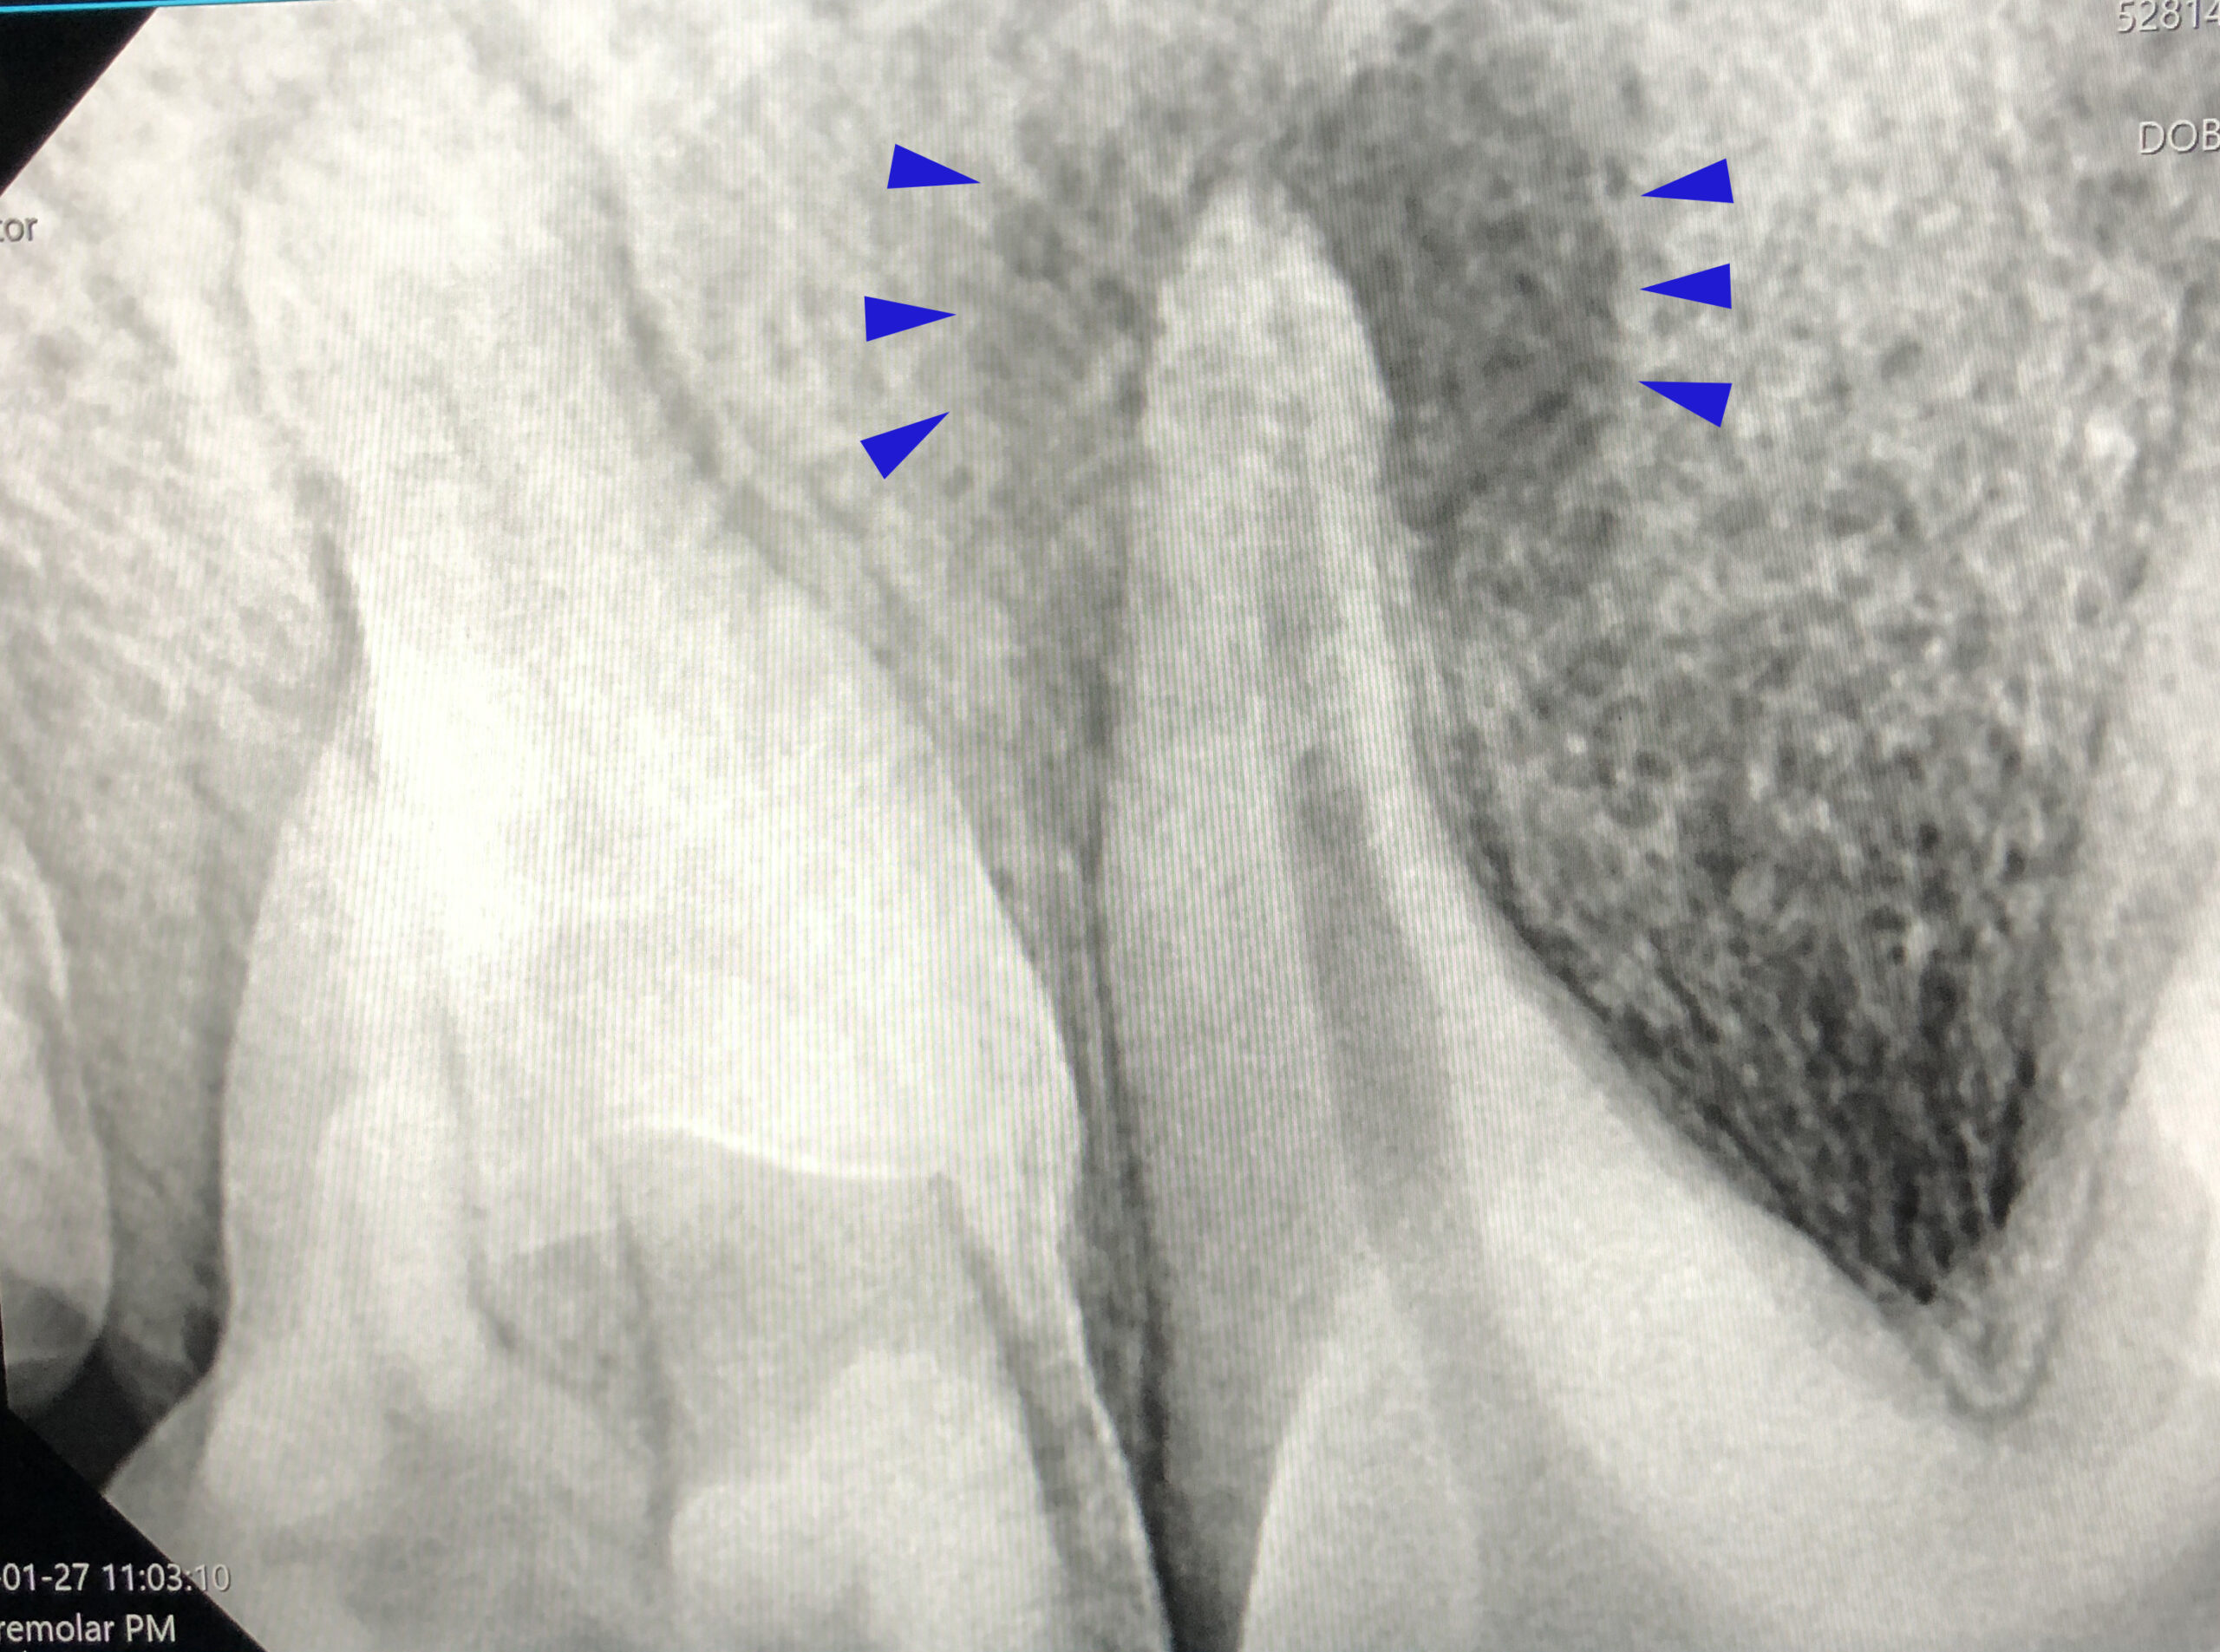

Onze praktijk beschikt over een dentale röntgenbuis. Deze buis is speciaal geschikt om kleine onderdelen op de foto te zetten. Tijdens gebitsbehandelingen kan het nodig zijn om de wortels van tanden of kiezen in beeld te brengen, zodat gerichter besloten kan worden of een extractie nodig is. Er kan met de foto goed bekeken worden of het glazuur is aangetast, of dat er wortels ontbreken of vergroeid zijn met het tandbeen, wat extractie bemoeilijkt.